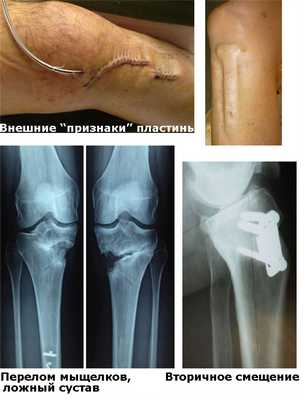

Этапы корригирующей остеотомии и остеосинтеза пластиной

Можно назвать такие осложнения, как: перелом плато большеберцовой кости; повреждение малоберцового нерва; нагноение в области операции; гиперкоррекция или наоборот, недостаточная коррекция; нестабильная фиксация и вторичные смещения; тромбоз глубоких вен и многое другое.

Осложнения остеосинтеза пластинами